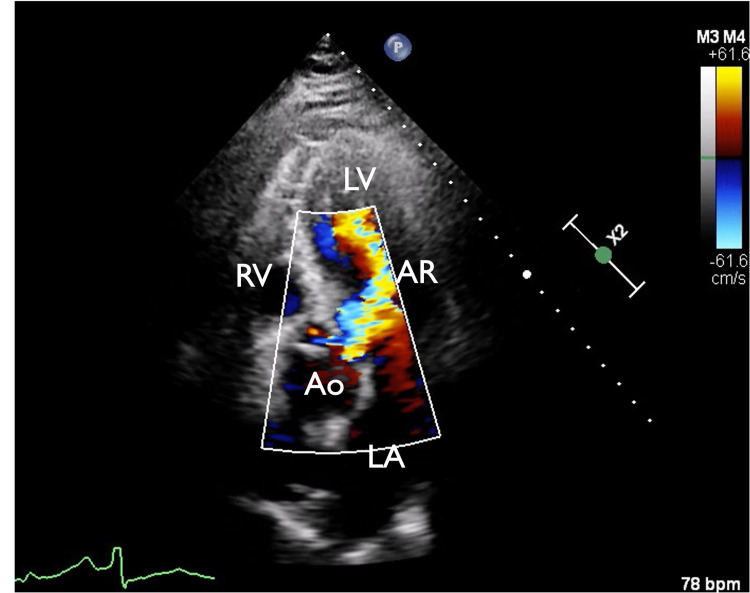

In view of chest pain associated with positive cardiac biomarkers, he was admitted to the Coronary Care Unit on intravenous nitroglycerin. While waiting for his admission, he suddenly had recurrent chest pain associated with marked hypotension (75/43 mmHg), for which the intravenous nitroglycerin was discontinued, fluid resuscitation was provided, and he was temporarily started on intravenous norepinephrine. The on-call cardiology team was contacted for an emergent evaluation. Subsequent ECG showed nonspecific ST-segment changes in leads V5-V6 (Figure 1). An emergent bedside echocardiogram revealed a moderate pericardial effusion of hemodynamic significance (Figure 2), as suggested by partial right ventricular chamber collapse (Figure 3) early in diastole and a plethoric non-collapsing inferior vena cava. The pericardial effusion also contained echogenic strands, which are highly concerning for blood clots. Additionally, a moderate to severe aortic valve insufficiency (Figure 4) was present according to color Doppler findings and pressure half-time assessment (315 ms). An intimal flap was visualized on the ascending and descending aorta, suggesting an extensive AD (Figures 2–6). A computer tomographic angiogram (CTA) of the chest and abdomen revealed a large pericardial effusion with an extensive AD extending from the level of the ascending aorta into his right brachiocephalic artery, the right and left common carotid arteries, and inferiorly to the right iliac artery (Figures 7–10), although not occlusive in diameter (or clinically). These findings were consistent with an extensive Stanford type-A AD with rupture into the pericardium, for which volume expansion and vasopressors were provided and emergently operated on the same day. The surgery included an open pericardiotomy with pericardial blood drainage, replacement of the ascending aorta from just above the commissure to the take-off of the innominate artery, partial replacement of the aortic arch, and aortic valve repair with successful results. Multiple intraoperative packed red blood cell units (8), fresh frozen plasma units (4), cryoprecipitate units (10), and platelet apheresis (3) were provided in view of bleeding complications related to the arrival provision of dual antiplatelet and anticoagulation therapy prior to the diagnosis of AD.